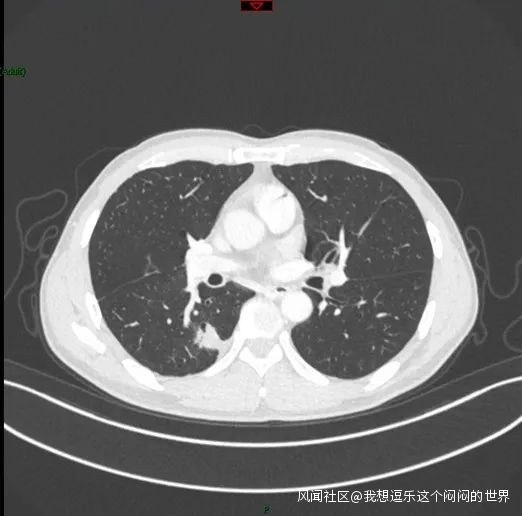

6月患者重新入院,複查了胸部CT。右下肺結節明顯增大,且胸膜結節也明顯增大,並出現了大量胸水。

右下肺結節增大,伴有胸腔積液、胸膜播散

患者入院後,進行了胸腔穿刺置管引流,放出了胸水,然後做了CT引導下的穿刺活檢,下一步根據病理和基因檢測結果進行治療。

因為已經出現了胸膜轉移,所以不考慮手術治療。